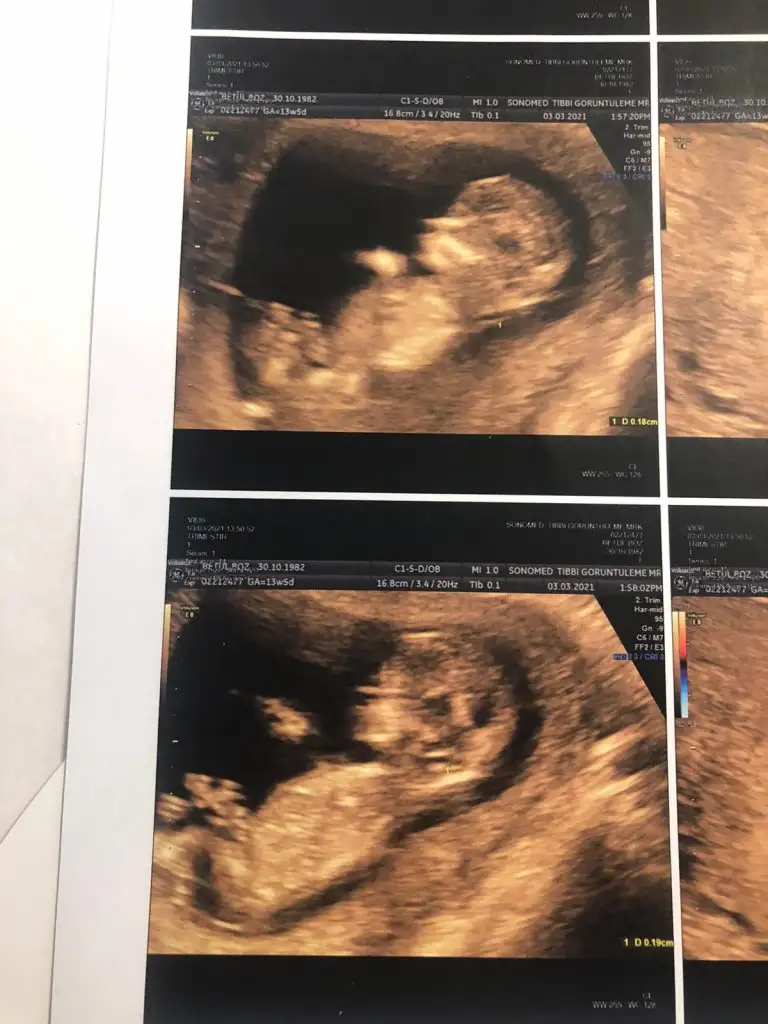

Merhaba daha önce görümcemin bebeginin cinsiyetini bildiniz. Şimdide yiyenin için rica ediyorum bakarmısın lütfen. 12 hafta karından. Ikra meyra Ikra meyra

• Screenshot_20210304_214724.webp

Screenshot_20210304_214724.webp

30 KB · Görüntüleme: 86